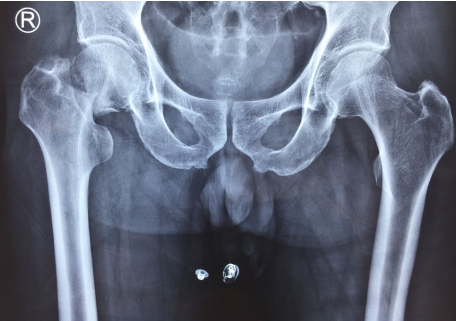

术前

78岁的许大爷家住安徽灵璧,3月28日不小心在家中摔倒,右髋部着地,当时就感到右髋部疼痛难忍,有块骨头似乎“支”了出来,在当地医院拍片显示股骨颈骨折。8小时后,许大爷被家人从灵璧送到betway在线登陆。

关节科邱东新副主任医师给许大爷作了仔细检查,建议手术,因为像许大爷这样的情形,手术越早开展,术后的并发症就越少。对于许大爷家人“老人这么大年纪了,这么大的手术,身体能不能吃得消,能不能承受的问题”,邱医生给他们讲,首先这种骨折是必须手术的,不手术带来的后果会更严重,后期长期卧床不能活动会带来血栓、肺炎、褥疮等多种风险,医学统计有30%的患者会在半年内死亡。其次,髋关节置换手术,这个普通人眼中的大手术,对于关节科医生来说,只是一个常规手术,经过邱东新医生团队的优化处理,已经可以做到无需插尿管,无需插引流管,也无需输血,手术时间也就一小时半左右,所以手术的风险也降到了最低,术后能够达到快速康复,很快就能恢复正常生活状态。讲明利弊后,许大爷及家人都同意进行手术。